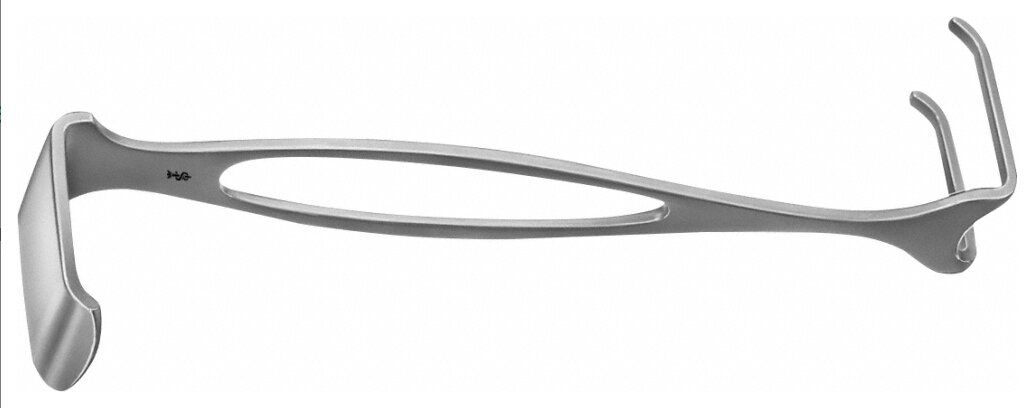

BT042R ~ WUNDHAKEN CZERNY 38X22MM 175MM ~

WUNDHAKEN CZERNY 38X22MM 175MM

Maulprofil

2 Zinken

Form

S-förmig gebogen, doppelendig

Maulteil

Blatt/Zahn

Spitze

stumpf/stumpf

Design

doppelendig

Maulbreite

22.00 mm

Typ Arbeitsende

Blatt / Zahn

Maulbreite 2

22.00 mm

Maultiefe

38.00 mm

Maultiefe 2

38.00 mm